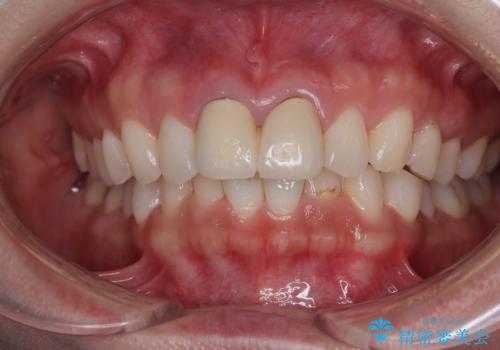

- 保険診療で装着した前歯の色調と厚みを気にして来院された患者様です。

黄ばみや厚みが改善され、まるで本物の歯のように調和した口元となりました。